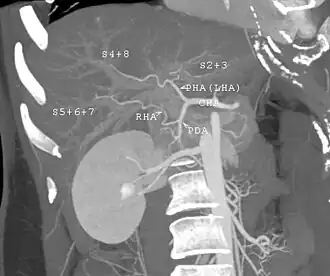

With the recent advances of noninvasive imaging, living liver donors usually have to undergo imaging examinations for liver anatomy to decide if the anatomy is feasible for donation. The evaluation is usually performed by multidetector row computed tomography (MDCT) and magnetic resonance imaging (MRI). MDCT is good in vascular anatomy and volumetry. MRI is used for biliary tree anatomy. Donors with very unusual vascular anatomy, which makes them unsuitable for donation, could be screened out to avoid unnecessary operations.

-

MDCT image. Arterial anatomy contraindicated for liver donation -

MDCT image. Portal venous anatomy contraindicated for liver donation -